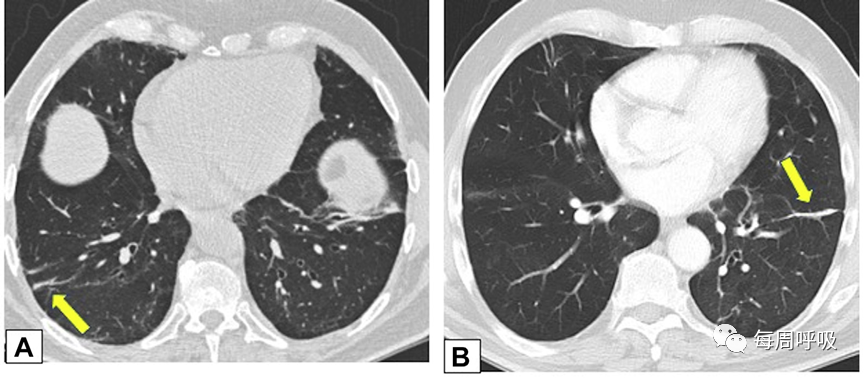

实变是OP病例中最常见的发现,发生在近75%的病例中,病变通常在双基底、支气管血管周围和/或外周(图2,3)。实变可以发生在肺的任何部位,边界清晰或模糊,呈游走性的特点(图4,5),可以呈局灶性,多发性和弥漫性,也可以表现为结节或肿块(图6)。实变常伴支气管充气征,可伴散在的磨玻璃样低密度或小实质结节。以主要的或完全的磨玻璃低密度为表现的较少见(图7)。磨玻璃低密度合并小叶间隔增厚可表现为铺路征(图8)。

图2 外周实变。2例患者CT轴位平扫图像。A,这张图片显示了一名女性右肺上叶周围实变,她曾因乳腺癌接受过放射治疗,并经活检证实为机化性肺炎(OP)。B,此图像显示左肺下叶和舌叶周围实变,活检证实为继发于淋巴瘤化疗的OP。

图3 支气管血管束分布 在活检证实的机化性肺炎患者中,通过中(A)和下(B)肺区的轴位增强CT扫描图像显示双侧多灶性支气管血管周围实变灶。